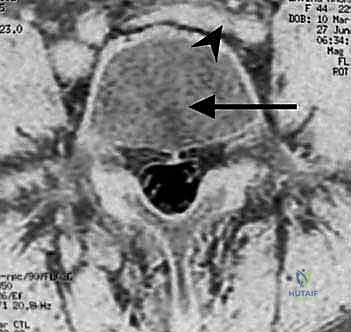

- التقييم التصويري المتقدم: إجراء صور الرنين المغناطيسي (MRI) والأشعة المقطعية (CT Scan) ثلاثية الأبعاد لتحديد مدى التلف بدقة متناهية.

الخطوة الثالثة: استئصال القرص التالف (Discectomy)

بمجرد كشف المنطقة، يتم استخدام أدوات الجراحة المجهرية الدقيقة لإزالة القرص الغضروفي التالف بالكامل. هذا الإجراء يزيل الضغط الفوري عن الأعصاب الشوكية المتضررة.